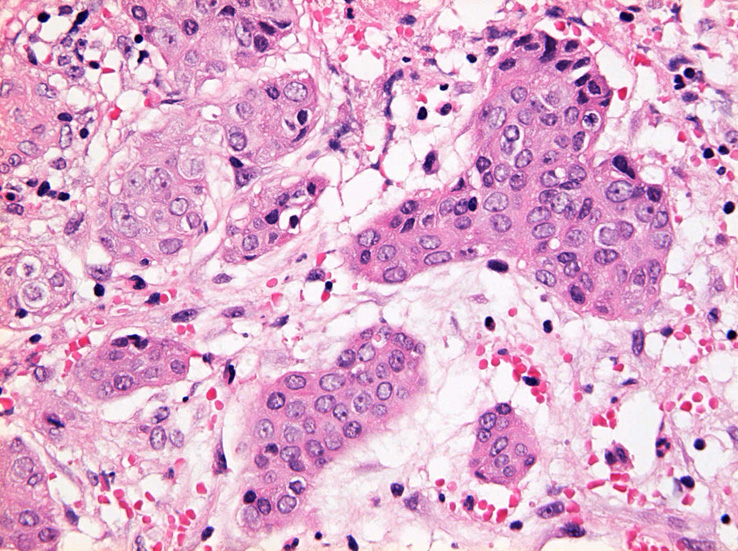

粘膜筋板直下に小型胞巣を作って浸潤し炎症性の間質をともなう。 浸潤性増殖のわりに細胞は均一, そんなに異型性も強くない。apoptosisに陥った細胞が散在する。部位によっては胞巣状増殖細胞は細胞間橋がありそうな扁平上皮様に見える。深いところは線維性間質が増えてきて細胞は索状となりcarcinoidなども鑑別候補となるかもしれない。明らかな腺管形成, 粘液産生はみられない。35歳男性, わりとおとなしい扁平上皮癌様の組織か?と生検初見時に考えられた。desmoplasticな間質にもよく観察するとバラけた細胞異型が認められる。 (腫瘍胞巣①, ③)

Hpf03.jpg

Hpf05.jpg

腫瘍胞巣①腫瘍胞巣②腫瘍胞巣③深い部分